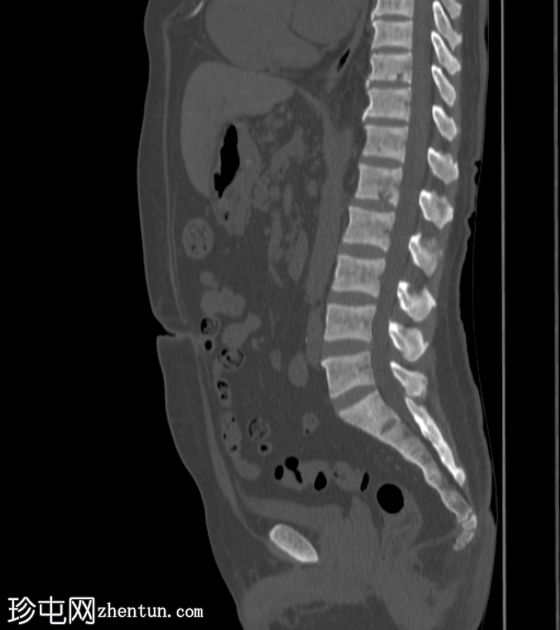

CT扫描

矢状位

骨窗

8.jpg

弥漫性骨硬化,提示肾性骨营养不良。